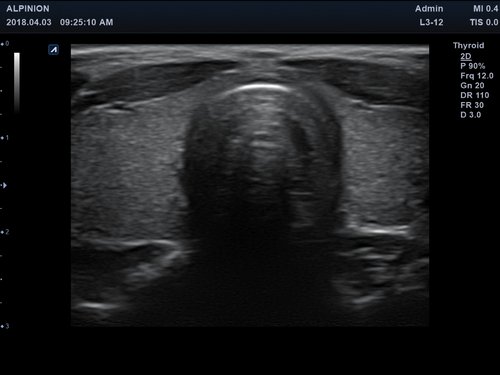

• Kleine Organe

Anwendungsbereiche Abdomen MSK, Nerven, Karotis, periphere Gefäße, Schilddrüse, Mamma

Ein Konvex-Schallkopf oder ein Linear-Schallkopf wird per USB-Verbindung an das Alpinion minisono angeschlossen werden.

Frequenz 1 - 6 MHz 3 - 12 MHz

Maße (Länge/ Breite/ Höhe) 25,5/ 62,5/ 157mm 25,2/ 62,5/ 150mm

Gewicht 5,8 oz/ 175g 5,6 oz/ 165 g